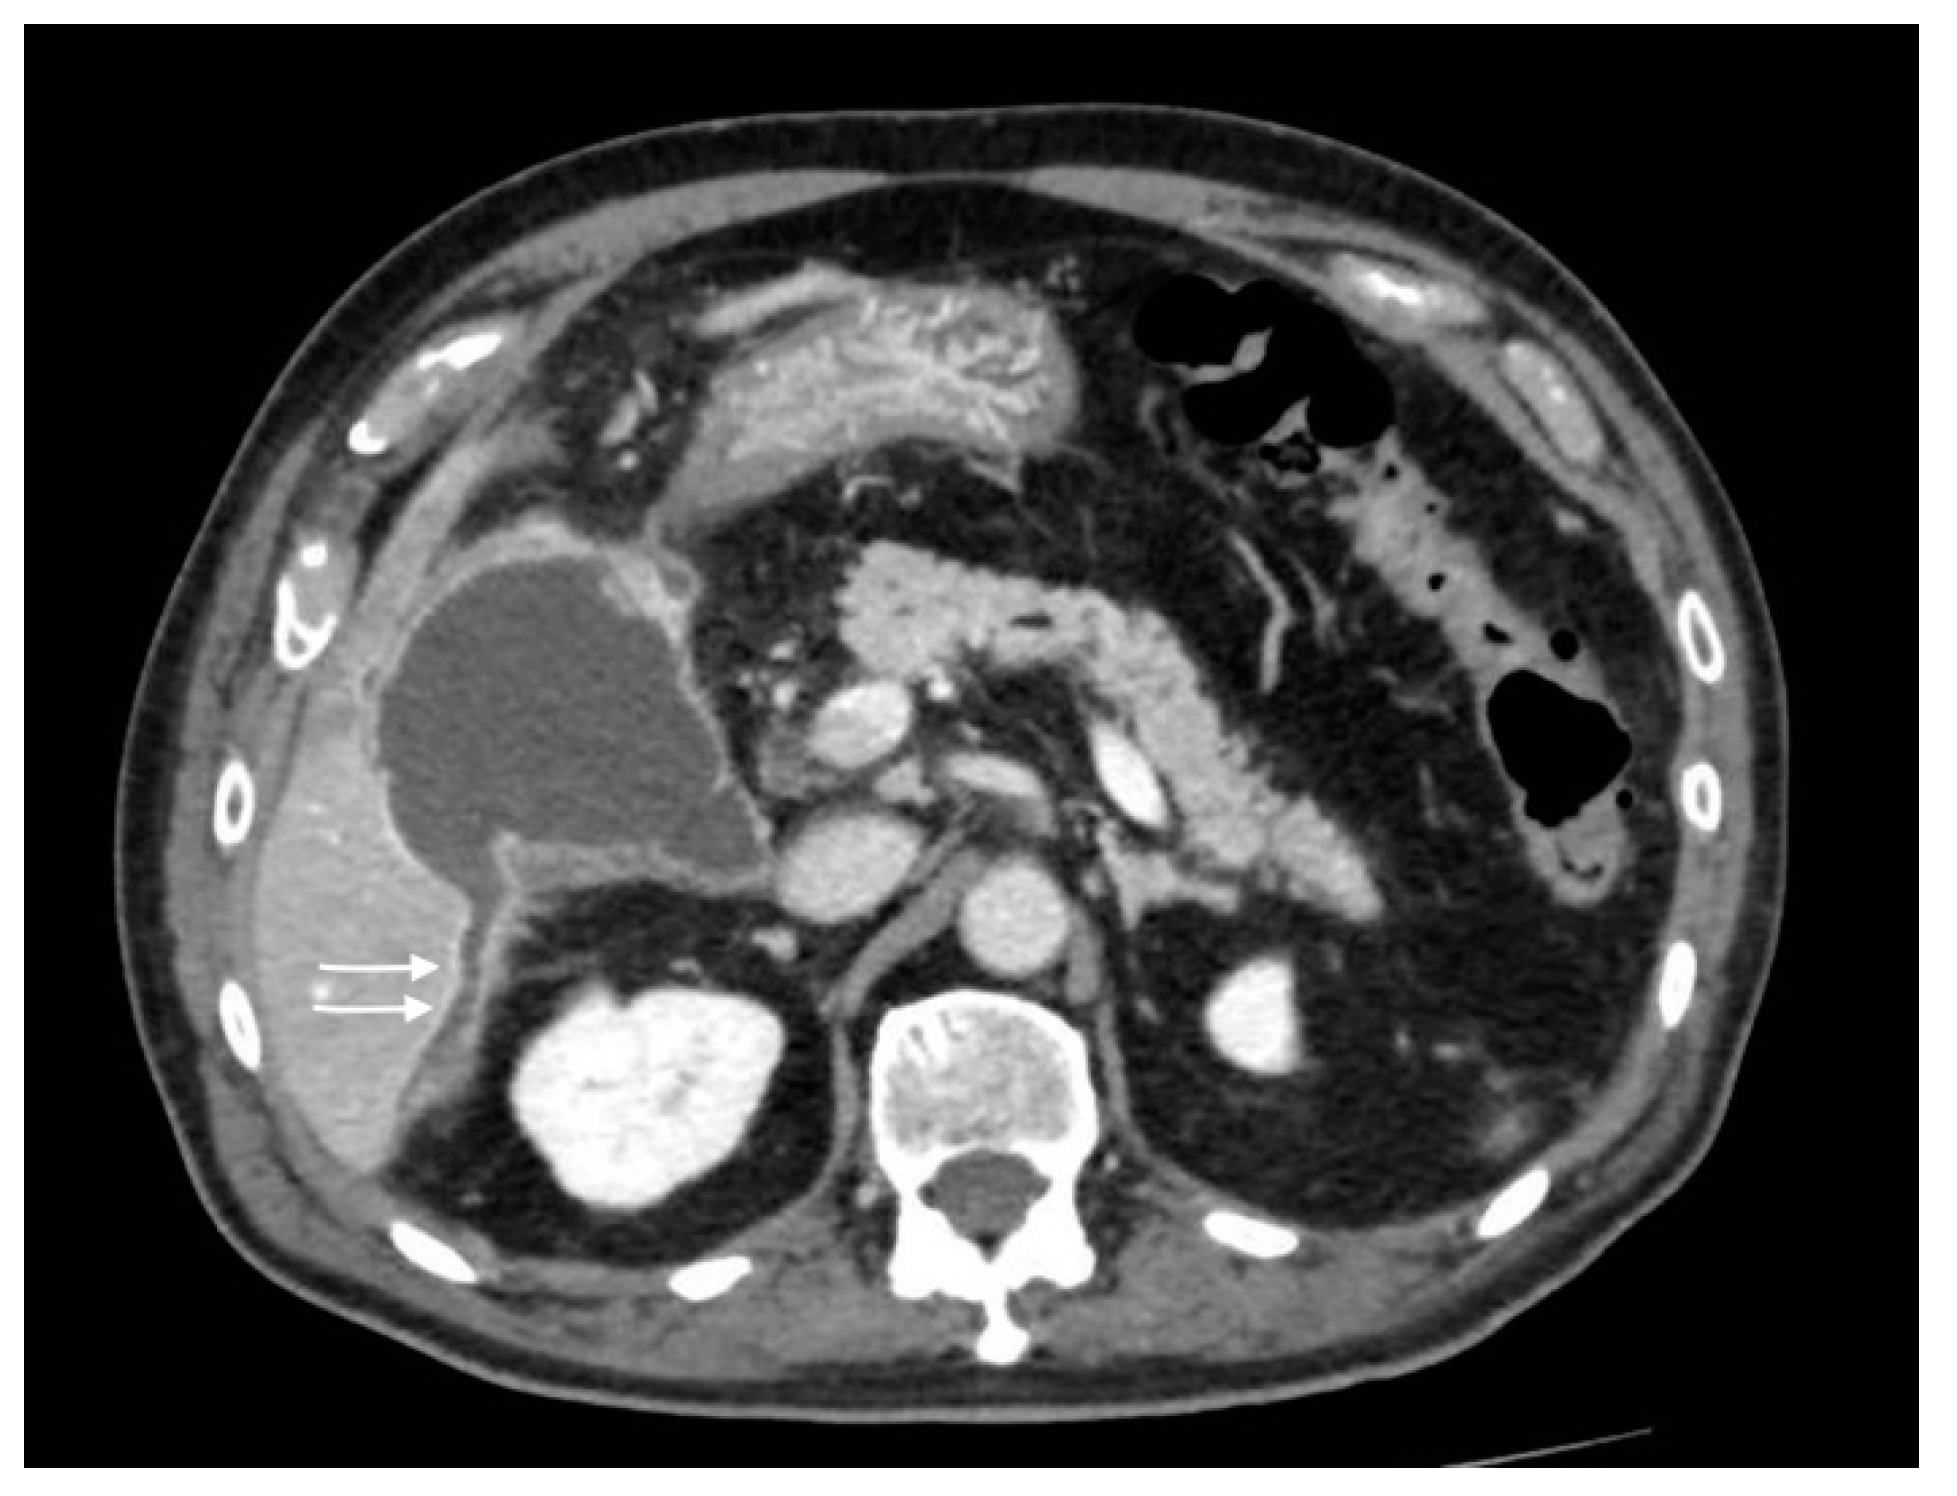

Figure 4.

Gallbladder perforation: transmural defect of the gallbladder wall (black arrow) with pericholecystic effusion (head arrows) and perihepatic peritoneal collection, suggestive of biliary peritonitis (white arrows).

Figure 5.

Gallbladder perforation: discontinuity of the gallbladder wall with fluid collection extended posteriorly to the right hepatic lobe (arrows).